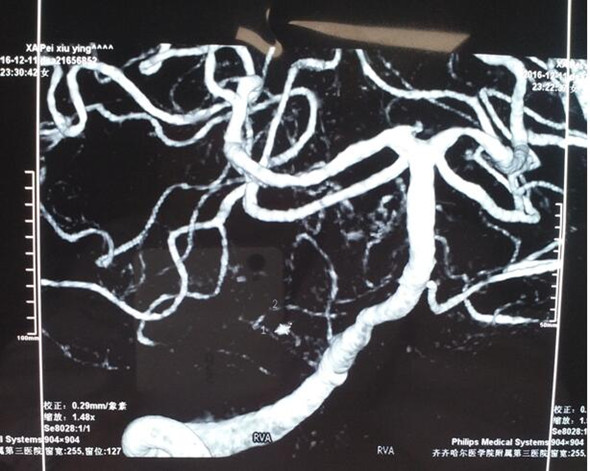

人们把脑动脉瘤形容为随时能爆炸的“不定时炸弹”,是非常凶险的出血性疾病,随时再次破裂出血,如若处理不当,患者随时可能因失去手术时机而导致死亡。入神经外二科后,副主任高风全凭借丰富的临床经验立即快速给予患者应对措施:镇静、控制血压平稳,积极联系介入科室行DSA(数字减影血管造影)检查,明确出血原因为:小脑后下动脉瘤破裂。

术前DSA造影检查